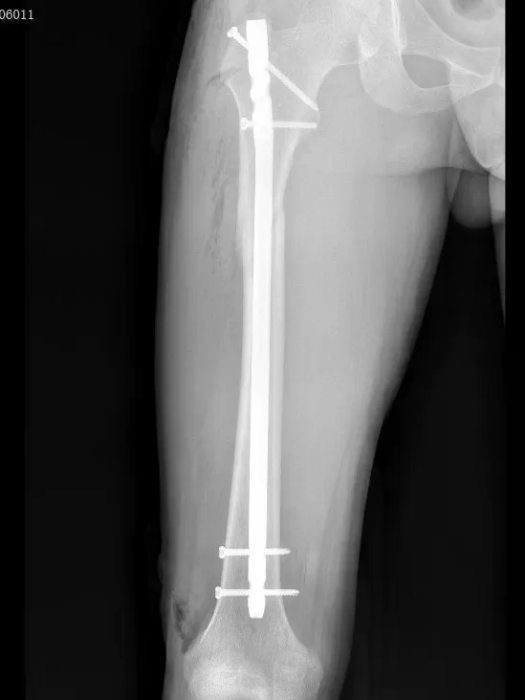

由李继松副主任医师、佘晗主治医师及刘兴医生组成的创伤团队的每一位成员都沉着应对、默契配合,在影像引导下精准定位骨折端,把控角度与深度,最终实现骨折端的完美复位。整个手术过程行云流水,既克服了该骨折复位难、固定要求高的技术痛点,又实现了微创化操作,术中出血量极少,患者生命体征平稳。历经1小时的精细雕琢,这台高难度手术以近乎完美的状态圆满结束。

术后,在骨科医护团队的细心指导与护理下,康复科同步介入,为患者制定个性化康复功能锻炼方案并全程指导,加速肢体功能恢复,术后第2天即可在床上进行简单肢体活动,疼痛症状明显缓解;术后1周,床上膝关节活动度达90°,髋关节活动度90°,肢体功能逐步恢复。复查影像学显示,骨折端复位精准、内固定位置稳固,完全达到临床理想标准,为后续愈合奠定了坚实基础。

此次手术的成功,既彰显了我院多学科协作的高效联动能力,更凸显了骨科团队在复杂骨折治疗中“精准诊断、精湛操作、沉着应变”的硬核实力。面对股骨粗隆下骨折这一“臭名昭著”的难治性骨折,医院以快速响应为基础,以技术突破为核心,用“严丝合缝”的完美手术证明了综合诊疗实力。